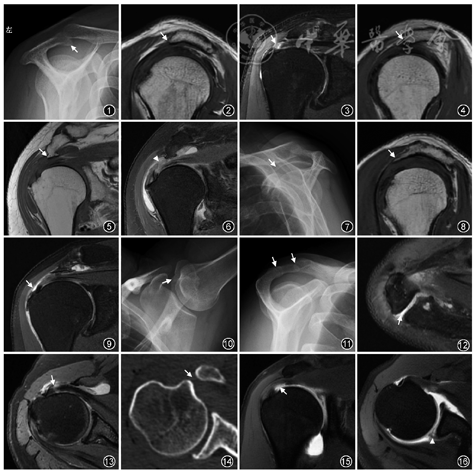

1.病因征象:(1)肩峰。肩峰形态一般在冈上肌出口位X线片上评估(图1),也可在CT/MR的斜矢状面上评估,MR观察层面一般为肩锁关节外侧的第一幅图像。肩峰形态分为4型,Ⅰ型为扁平形,Ⅱ型为弓形,Ⅲ型为钩形,Ⅳ型为凸面向下的反弓形,其中Ⅲ型肩峰最易引起肩峰下撞击(图2,3)。正常的肩峰斜面约呈水平或稍向前上倾斜,肩峰向前下或外下倾斜、肩峰低平均可能造成肩峰下间隙狭窄(图4)。肩峰下骨刺常提示存在长期的慢性撞击(图5,6)。(2)肩锁关节。肩锁关节退变时可出现骨质增生肥大伴下缘骨刺形成,关节积液,关节囊增厚,有可能与肩袖发生撞击。(3)喙肩韧带。喙肩韧带增厚、钙化在斜矢状面上显示最佳,其肩峰附着处可有骨刺形成,尖端指向喙突(图7, 8, 9)。(4)肩峰小骨。肩峰次骨化中心通常在22~25岁骨化完成,如果骨化中心未能如期愈合,未愈合的部分就称为肩峰小骨[2],在X线腋轴位或CT/MR横断面上观察最佳,在冈上肌出口位或CT/MR的斜矢状面上有时可见“双肩锁关节征”(图10, 11, 12)。肩峰小骨可以不稳定,其软骨结合处或假关节下缘还可有骨刺形成,引起与肩袖的撞击。在MRI上当软骨结合处出现液性高信号时常提示肩峰小骨不稳[5]。软骨结合处还可出现硬化、软骨下囊变及骨髓水肿。(5)肩峰下间隙(acromio-humeralinterval,AHI)。AHI的宽度因人而异,目前多认为AHI越小,撞击发生的概率越高。多项研究发现,当AHI<7 mm时诊断肩峰下撞击综合征及肩袖损伤的准确性较高[6]。但有文献报道,AHI与肩关节体位及肌肉活动相关,最小AHI值随肩关节外展角度的增大而减小,在不同外展角度时施加负荷,外展肌收缩时的AHI值均小于内收肌收缩时的AHI[7, 8]。因此功能位MRI可能更有助于寻找肩峰下撞击的病因。

影像学检查可以为本病的诊断提供依据。多项研究发现,喙肱间距(coracoid-humeral distance, CHD)变窄、喙突指数(coracoidindex,CI)增大时,易发生喙突下撞击[10, 11]。CHD是指喙突到肱骨小结节之间的最短距离,其测量受体位因素影响,正常人中立位时通常为8.7~11.0 mm,当上臂屈曲内旋时可缩短至6.8 mm[12]。CI是指CT/MR横断面图像上喙突向外侧延伸超出关节盂平面的距离。当CI>8.2 mm时,容易引起喙突下撞击[13]。撞击可以导致喙突下间隙内及周围结构的损伤,包括肩胛下肌腱撕裂,在液体敏感序列上肌腱内出现液性高信号,喙突下滑囊积液,肱二头肌长头腱腱鞘水肿,喙突及肱骨小结节处出现囊变、骨髓水肿或骨质增生等(图13,14)。

肩关节MR平扫和关节造影有助于发现内撞击导致的肩袖、盂唇和肱骨头损伤(图15,16)[5, 15]。肩袖损伤多位于冈上肌腱后部和(或)冈下肌腱上部的关节侧,出现磨损或部分撕裂,在液体敏感序列上肌腱关节侧边缘毛糙或信号增高。盂唇损伤主要表现为后上盂唇磨损或撕裂,可伴有上盂唇损伤,但很少出现唇旁囊肿。与MR平扫相比,MR关节造影特别是在外展外旋位时,能够更好地显示后上部盂唇和肩袖关节面的撕裂。在外展外旋位时,定位线垂直于后上部肩袖肌腱,没有容积效应的干扰,后上部关节囊内充盈对比剂,肩袖肌腱张力减低并不再紧贴肱骨头,使得对比剂更容易进入后上部肩袖关节面和盂唇的撕裂口,因此更有助于损伤的检出。肱骨头后上部损伤时可以出现局部骨皮质凹陷、皮质下囊变及骨髓水肿。